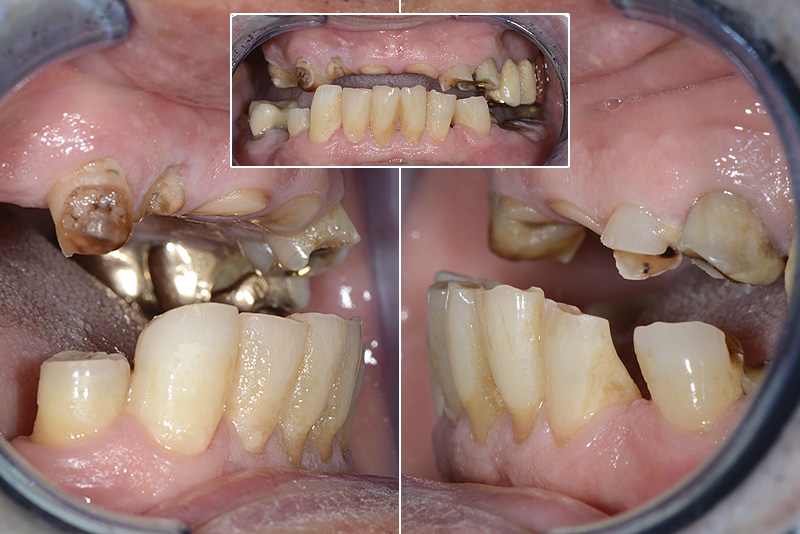

PREMESSA: in seguito all’estrazione dell’incisivo laterale superiore di destra, resasi necessaria per cause batteriche, si decide di affrontare il caso con il posizionamento di un impianto in sostituzione dell’elemento mancante dopo guarigione del sito infetto. Con tecniche rigenerative sia dei tessuti ossei mancanti a causa dell’infezione pregressa, sia dei tessuti gengivali che appaiono inizialmente troppo spostati in alto, si ripristina una corretta morfologia delle parabole (contorni) gengivali e delle papille interdentali (triangoli di gengiva tra due denti vicini).

Vengono utilizzati 2 tipi di provvisori: il primo, cementato ai denti vicini, viene utilizzato dal momento dell’estrazione del dente fino ad impianto osteointegrato (circa 6 mesi); il secondo, avvitato direttamente all’impianto, ha una funzione di prova estetica ma soprattutto di guida per la maturazione dei tessuti gengivali peri-implantari portandoli verso la maturazione completa prima di posizionare la corona finale in disilicato di litio.